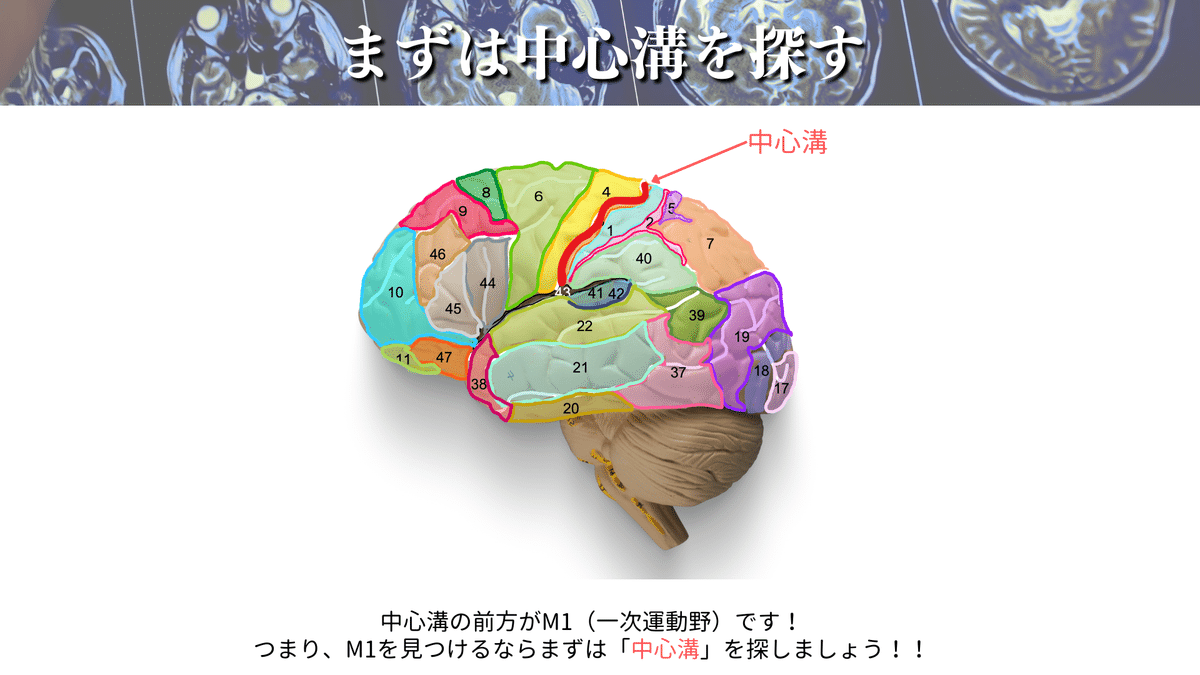

M1を探すなら、まずは「中心溝」を探しましょう!

なぜなら、M1は中心前回に位置しており、中心前回は中心溝の前にある脳回だからその名前がついています👍

⬇️のポイントを押えることで、ほとんどの場合に対応できるかと思います☝️

特に僕のおすすめは「pM bracket sing」「handkob sing」「Bified post CG sing」の3つです!

この3つだけでも結構な確率で見つけられますが、6つ全てを押さえておくとより安心かと思います👍

ここまでで、「中心溝」を見つけられたと思いますので、その前方にある「中心前回(M1)」も見つけられたと思います✨